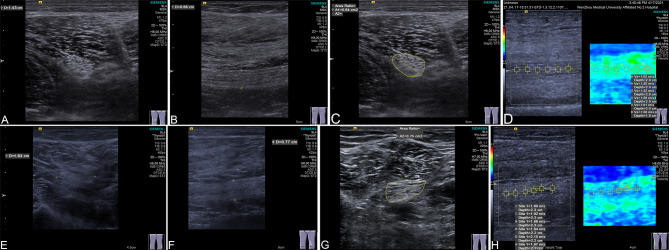

Method: 182 patients with T2DM, 137 patients with diabetic polyneuropathy, and 198 healthy volunteers were included in this retrospective cross-sectional diagnostic study. Sciatic neuropathy was evaluated through Doppler ultrasound examination with a VTIQ quantitative analysis system to acquire elastic modulus, cross-sectional area (CSA) and shear wave velocity (SWV). Nerve conduction velocity (NCV) was also evaluated via neurophysiological examination. Logistic regression was used to analyze odds ratios (OR) related diabetic polyneuropathy. The diagnostic accuracy of the VTIQ technique-acquired index on diabetic polyneuropathy was analyzed using the receiver operating characteristic (ROC) curve.

Results: VTIQ technique-acquired indexes all differed significantly among three study groups, among which Elastic modulus and CSA were independently related to diabetic polyneuropathy risk according to the logistic regression analysis. NCV was also an independent risk factor for diabetic polyneuropathy. ROC analysis revealed that Elastic modulus, CSA and NCV can distinguish diabetic polyneuropathy patients from T2DM cases with the AUC of 0.797, 0.654 and 0.775 respectively. But their combination achieved the highest diagnostic value (AUC = 0.883). CSA and SWV of the sciatic nerve are positively correlated with visual analog scale (VAS) scores.